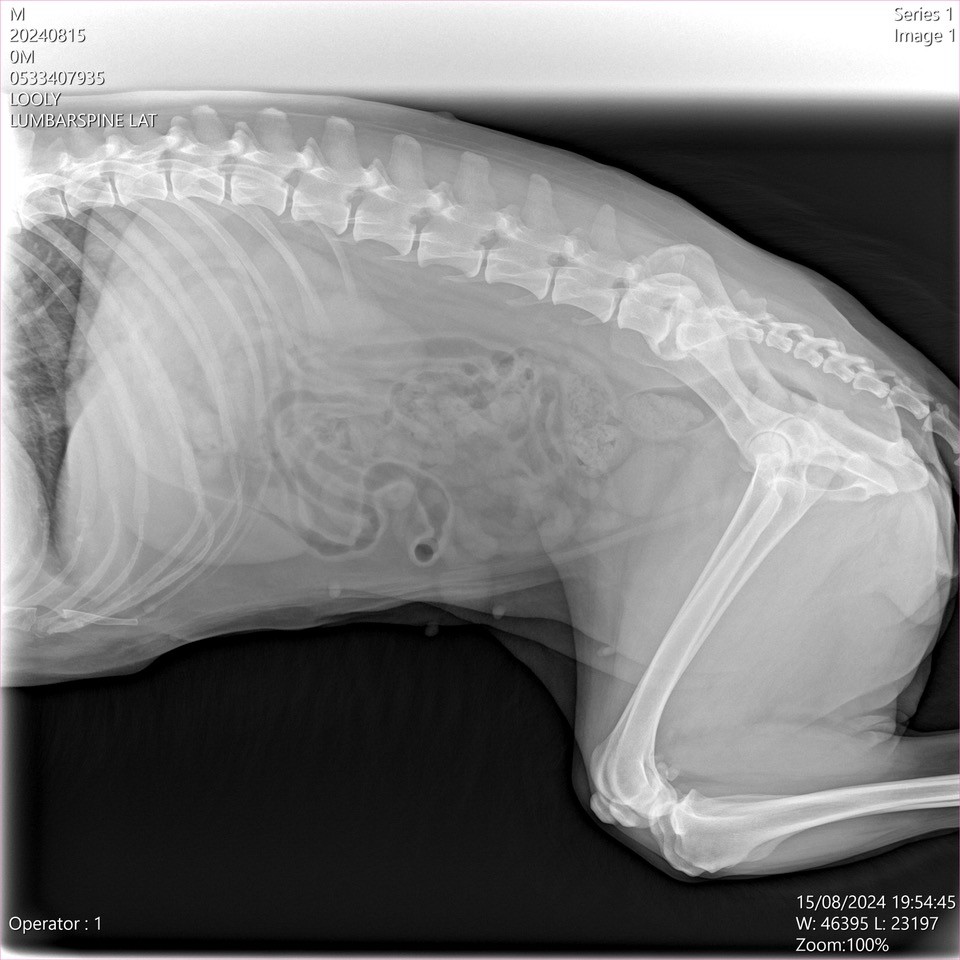

X-ray